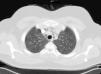

Se trata de un paciente varón de 24 años, que consultó en urgencias por la aparición súbita de dolor precordial intenso irradiado a la espalda, con mareo no giratorio y cierta dificultad respiratoria por el dolor. Interrogado, sólo refería una ligera rinitis acuosa desde unos 4 días antes, sin tratamiento. No era fumador ni tenía otros antecedentes de interés. La exploración física no mostraba alteraciones. En los análisis destacaba leucocitosis de 18,7×103 con 16,6×103 neutrófilos/ul. La proteína C reactiva era de 20,3mg/l Se realizó una extracción para gases arteriales respirando aire ambiente que mostró pH 7,42, Pa02 54mmHg, PaCO2 35mmHg y HCO3 23 mmol/l. El electrocardiograma mostraba un ritmo sinusal con 115 lpm e imagen de S1Q3. En la radiografía de tórax se observaba una delgada línea de neumopericardio. Para descartar embolismo pulmonar se realizó un angio-TC de tórax que no apreció defectos vasculares y confirmó la presencia de aire en el espacio mediastínico (fig. 1) y neumopericardio. El paciente recibió tratamiento analgésico y oxígeno. A las 24 horas estaba asintomático, con saturación de oxihemoglobina del 98% (con Fi02 0,21) y se había normalizado la leucocitosis.